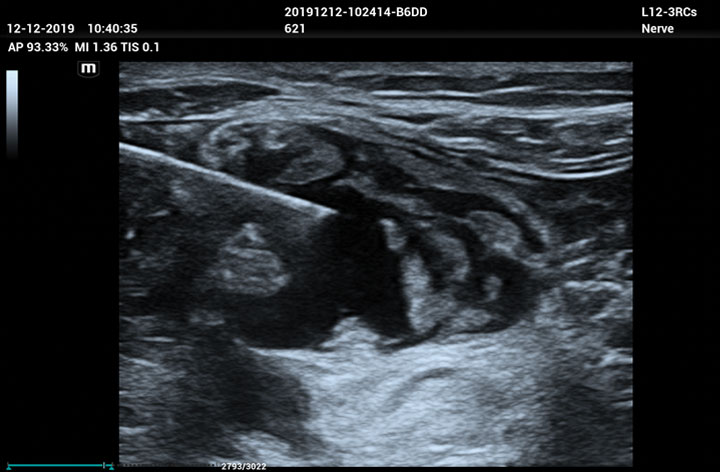

The ME8 Ultrasound System has been thoughtfully designed to overcome the obstacles clinicians face in today’s challenging healthcare environment. Powered by our groundbreaking software-based beamformer technology, ZONE Sonography® Technology+(ZST+), the ME8 Ultrasound System empowers decision-making by providing end-users best-in-class image quality and access to a comprehensive suite of workflow enhancement tools.

Advanced Technologies

Enhancing Clinical Confidence